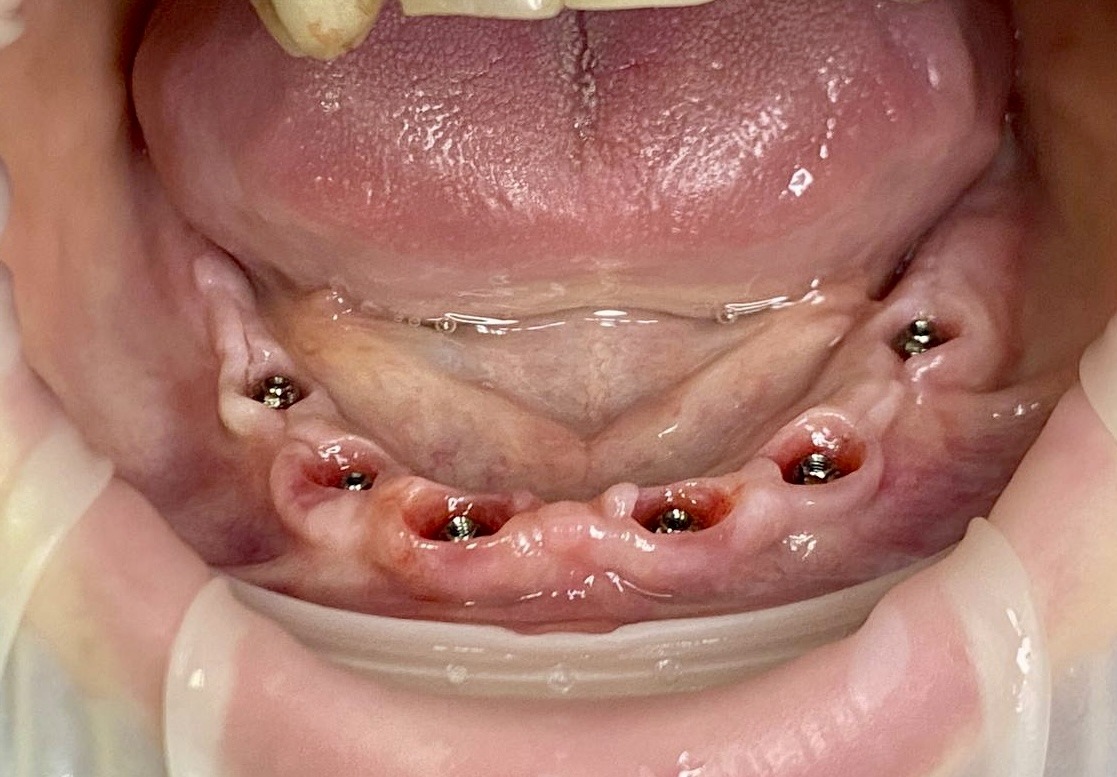

Имплантация по методу all-on-6 на имплантатах Neodent

Пациентка обратилась для имплантации и протезирования нижней челюсти, так как после обследования у терапевта и анализа 3D снимка , были показания к удалению 5 зубов.

После консультации у стоматолога-хирурга была выбрана имплантация по методу all-on-6.

На выбор этого метода повлияла возможность не ожидать 4-6 месяцев приживления имплантатов, а сразу провести протезирование шинирующим акриловым протезом, что было важно для пациентки. В работе использованы имплантаты Neodent. Работа выполнена за 6 дней.